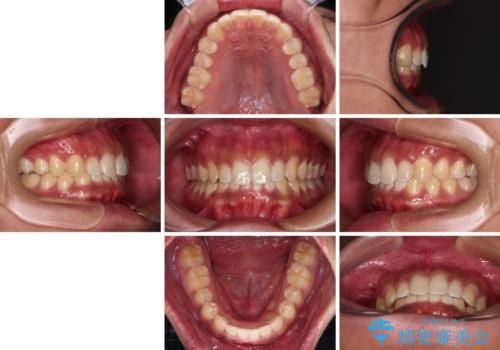

デコボコとディープバイトを治したい インビザラインによる矯正治療

気になっていたデコボコや隙間は改善し、きれいな歯列に整えることができました。

咬合力が非常に強い方であったため、これ以上のディープバイトの改善は困難となりました。